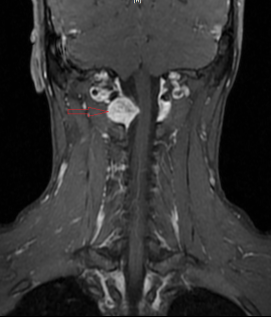

近期,富顺县中医医院脑病科成功为一名脊髓硬膜外神经鞘瘤患者进行手术治疗,为患者解除了长期的病痛折磨。该患者在2年前无诱因出现阵发性双手、双小腿麻木、乏力,偶伴头晕、黑矇等症状,在我院接受颅脑磁共振检查后发现其颈1-2水平脊髓外异常占位,考虑神经鞘瘤(图中红色箭头标注)。